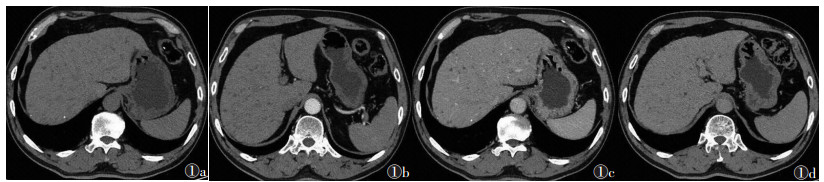

2 结果5例中,粟粒型肝结核2例,结节型肝结核3例。①粟粒型肝结核:CT图像上均可见肝脏增大,1例可见脾脏增大;2例均可见肝内散在多发小囊样低密度灶(1例伴小钙化灶),直径0.6~2.0 cm,动脉期、静脉期及延迟期均无强化(图 1)。②结节型肝结核:病灶直径均>2.0 cm,表现为肝内单发或多发略低密度灶,CT值41~50 HU,增强扫描延迟期轻度强化,1例病灶内可见“簇征”或“蜂窝征”(图 2)。

| 图 1 男,53岁,粟粒型肝结核 图 1a ~ 1d 分别为CT平扫、增强扫描动脉期、门静脉期和延迟期图像。平扫可见肝脏增大,肝实质内多发不规则形囊样低密度影,肝顶部可见2处高密度钙化影;注射对比剂后肝内病灶未见强化,增强扫描肝内病灶数量较平扫增多 |